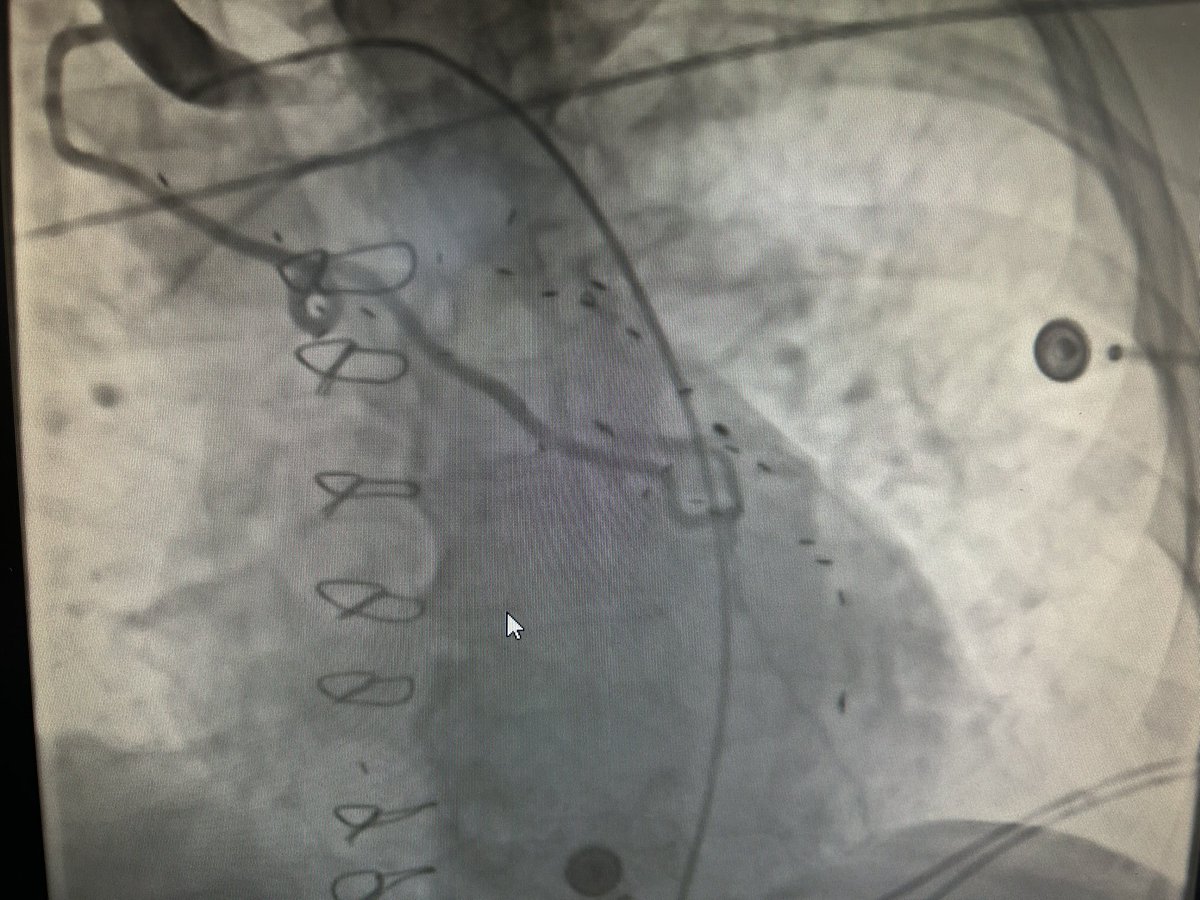

85 yo F part of the low risk TAVR vs SAVR Evolut trial who received 26mm CEV in 2017. Now with severe AS and high risk sinus sequestration for TAV in TAV. TAVR explant with redo SAVR. Growing pandemic or a one off??? #TAVR #sapien #corevalve #SAVR

Stephane Leung, MD MSc FRCSC tweet media